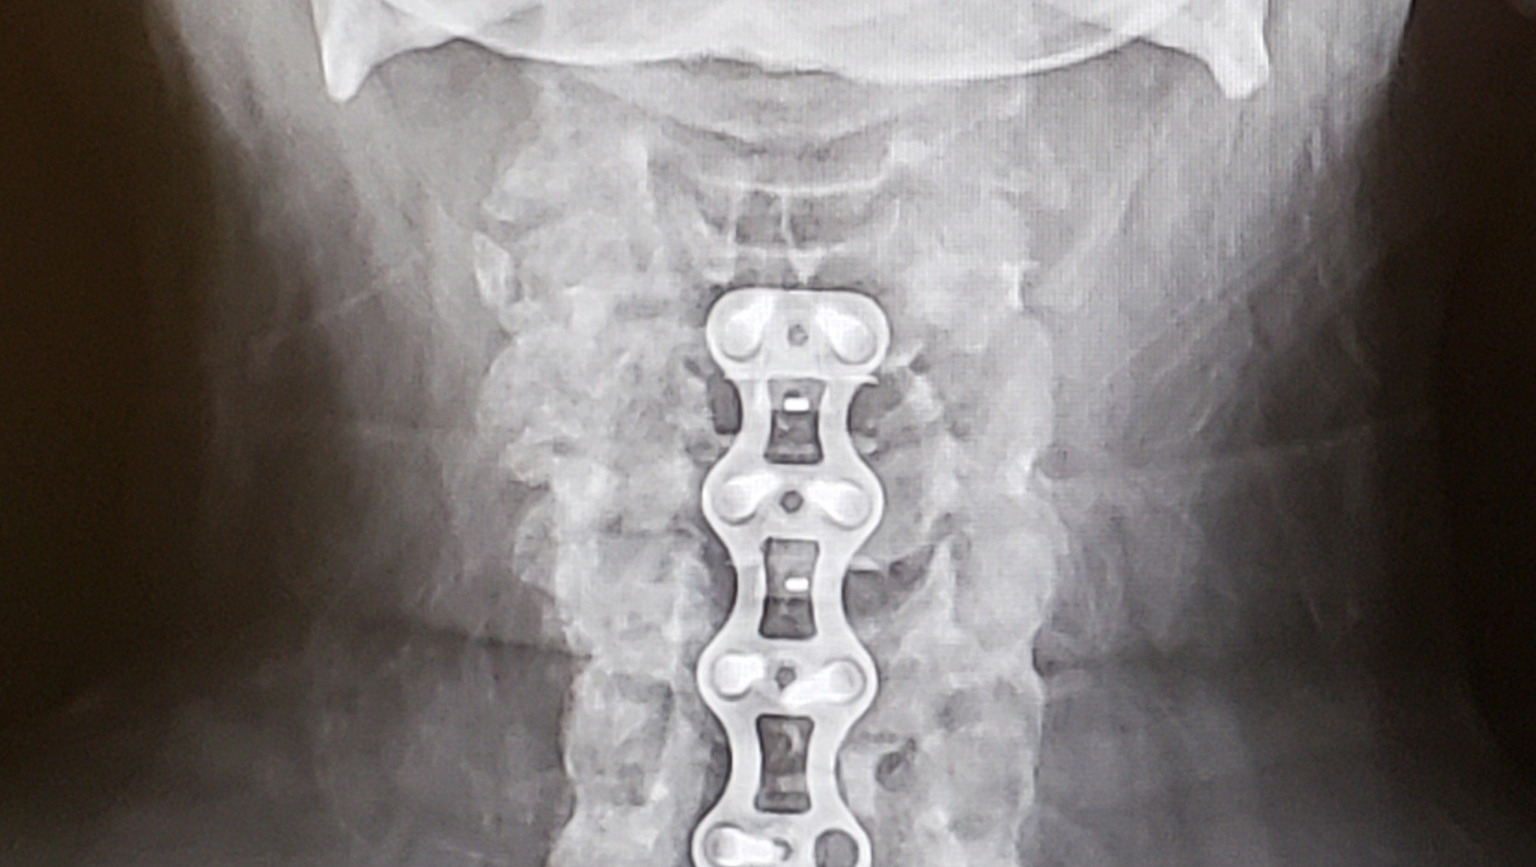

Hello, my name is Tamyra Carter. Unfortunately, I have lost finances due to recovering from a lower leg fracture and extensive neck surgery. I've been scared and embarrassed to write this, but I had a friend encourage me to do so. I am unable to work yet until neck heals. So, that is taking a toll as well. If possible, please consider giving to help w/ rent, utilities, food, etc. Thank you so much!

-ski accident, first neck surgery and off work for over a year.